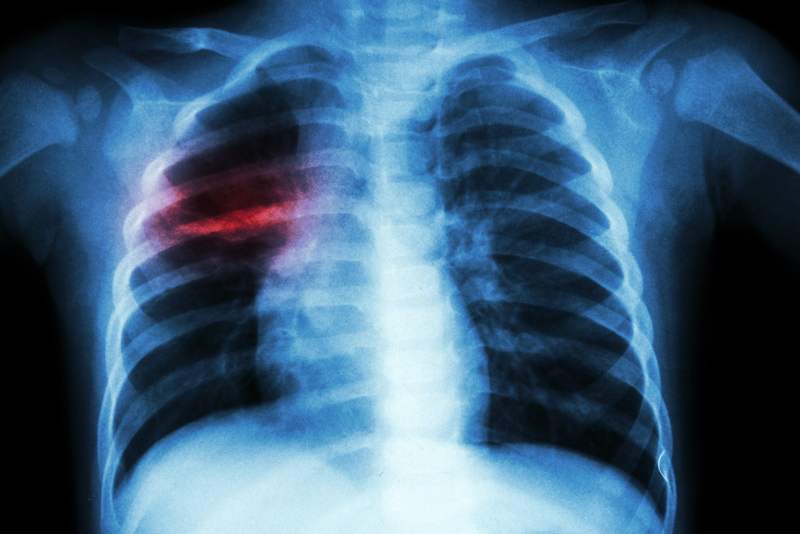

The immune system walls off the microbes in most infected people, keeping them healthy. But some infected individuals develop the active form of the disease, with symptoms such as a bloody cough, chest pain, fever, weakness and loss of appetite. The researchers focused on investigating how often children catch TB from an infected family member and go on to develop the active disease.